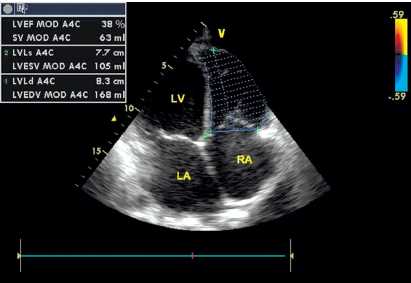

По данным трансторакальной эхокардиографии (ЭХО-КГ, рис. 3), выявлено расширение полости правого желудочка (ПЖ) со снижением его сократительной способности (фракция выброса ПЖ составила 39%), увеличение полости правого предсердия до 6,1 × 4,6 см и левого предсердия до 5,6 × 5,0 см. КДО ПЖ — 164 мл; КСО ПЖ — 102 мл. При изучении левого желудочка (ЛЖ) патологии выявлено не было, ФВ ЛЖ – 51%. Нижняя полая вена не расширена, диаметр — 2,0 см, коллабировала на вдохе более 50%. Данных о врождённом пороке сердца не выявлено.

Рисунок 3. Эхокардиограмма больного В. Расширение предсердий и правого желудочка.

Примечание: ЛП — левое предсердие; ПП — правое предсердие; ЛЖ — левый желудочек; ПЖ — правый желудочек; КСР — конечно-систолический размер; КДР — конечно-диастолический размер; КСО — конечно-систолический объем; КДО — конечно-диастолический объем; ФВ — фракция выброса.